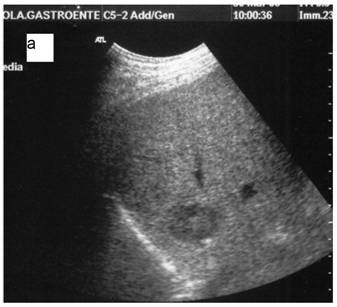

The Diagnosis Of cirrhosis By High Resolution ultrasound Of ...

The diagnosis of cirrhosis by high resolution ultrasound of the liver surface VSïIMONOVSKYŁ, MD Clinic of Imaging Methods, Faculty Hospital Motol and 2nd Medical Faculty of Charles University, Praha, ... Doc Retrieval

Morphologic cirrhosis Diagnosis From Ultrasound

Morphologic cirrhosis diagnosis from Ultrasound of the ultrasound (US) imaging and its widespread presence reliable sign in the detection of liver cirrhosis and can have a diagnostic accuracy of 70% or more. [10] showed that ... Doc Viewer